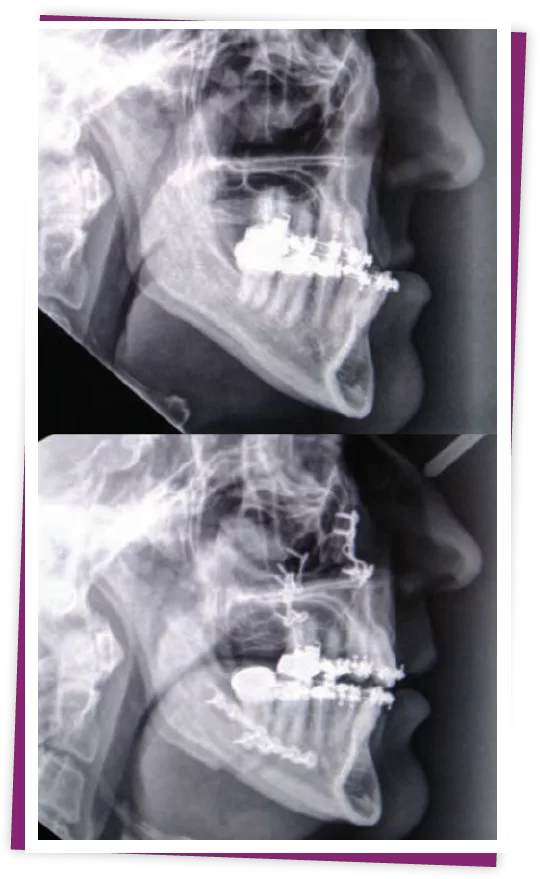

Thông thường các trường hợp cần điều chỉnh răng sẽ được can thiệp hoàn thiện chỉnh nha trước, sau đó mới phẫu thuật chỉnh móm. Hoặc cũng có thể phẫu thuật trước sau đó chỉnh nha hoàn thiện khớp cắn.

Bước 5: Thực hiện phẫu thuật hàm. Sau khi gây mê, bác sĩ sẽ thực hiện phẫu thuật dựa vào kế hoạch cụ thể đã thống nhất trước đó.

Phẫu thuật chỉnh móm được thực hiện tại Kubet theo quy định của Bộ Y tế. Bác sĩ tiến hành gây mê và tùy tình trạng móm của bạn mà bác sĩ sẽ thực hiện.

Sau khi chỉnh sửa vị trí tối ưu của 2 hàm, xương được cố định lại bằng nẹp vít cứng chắc, mang đến sự cân đối cho hai hàm, khớp cắn khít nhau, hỗ trợ việc ăn nhai.